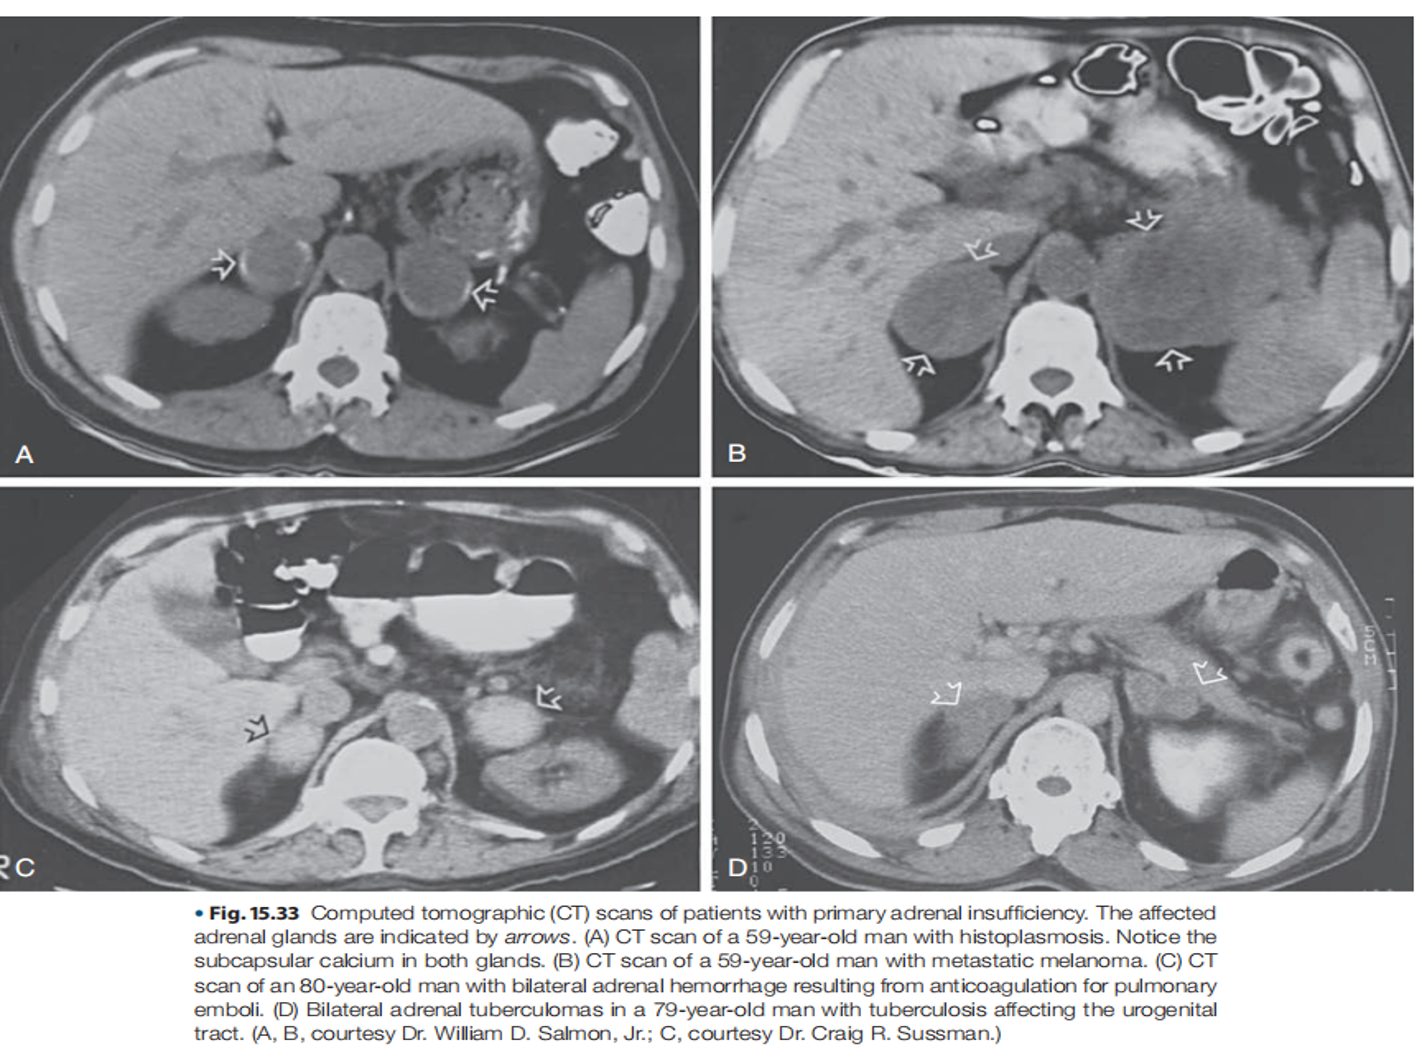

- Infections: Tuberculosis, fungal infections, and HIV can damage the adrenal glands.

- Hemorrhage: Bleeding into the adrenal glands, often seen in conditions like Waterhouse-Friderichsen syndrome (associated with meningococcal infection).